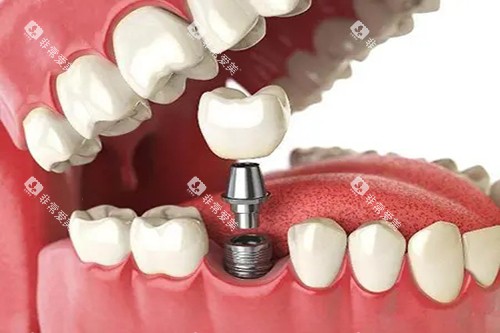

在种植牙方面,医院采用德国卡瓦智能化导航系统,支持即刻种植、ALL - ON - 4/6全口修复,误差控制在0.1mm,单颗种植周期缩短至1小时,大大提高了种植效率和精密度。

在种植牙方面,智能化导板种植技术提升了种植精度,减少了手术创伤,多位患者提到种植后咬合功能修复快,全瓷牙冠修复成效自然。